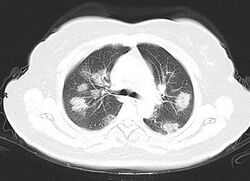

Chest CT scans may be helpful to diagnose COVID‑19 in individuals with a high clinical suspicion of infection but are not recommended for routine screening.[129][141] Bilateral multilobar ground-glass opacities with a peripheral, asymmetric, and posterior distribution are common in early infection.[129][142] Subpleural dominance, crazy paving (lobular septal thickening with variable alveolar filling), and consolidation may appear as the disease progresses.[129][143] Characteristic imaging features on chest radiographs and computed tomography (CT) of people who are symptomatic include asymmetric peripheral ground-glass opacities without pleural effusions.[144]

Many groups have created COVID‑19 datasets that include imagery such as the Italian Radiological Society which has compiled an international online database of imaging findings for confirmed cases.[145] Due to overlap with other infections such as adenovirus, imaging without confirmation by rRT-PCR is of limited specificity in identifying COVID‑19.[144] A large study in China compared chest CT results to PCR and demonstrated that though imaging is less specific for the infection, it is faster and more sensitive.[128]